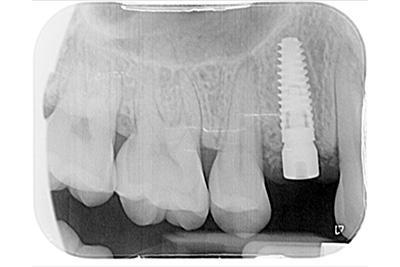

Implants in position and waiting on integration – 4 to 6 Month